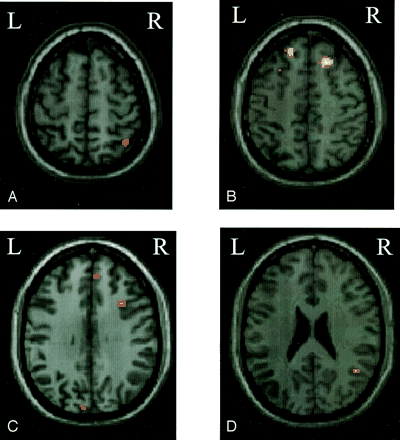

Compared with patients who went on to develop MS, those patients with no evolution had more significant activations of the contralateral primary SMC (SPM space coordinates: −20, −28, 64), contralateral SMA (SPM space coordinates: −4, 0, 60), ipsilateral parietal portion of the paracentral lobule (SPM space coordinates: 6, −46, 64), and ipsilateral cerebellar hemisphere (SPM space coordinates: 18, −58, −22) (Fig 1). On the contrary, compared with those patients without a disease evolution, patients who developed MS had more significant (bilateral) activations of the SFS (SPM space coordinates: 24, 26, 52 and −26, 18, 52), the superior frontal gyrus (SFG) (SPM space coordinates: 6, 50, 46 and −6, 36, 50), the IPS (SPM space coordinates: 40, −56, 60 and −30, −74, 36) (Fig 2), and the putamen (SPM space coordinates: 20, 2, 10 and −18, 2, 14). They also showed more significant activations of the ipsilateral MFG (SPM space coordinates: 34, 16, 34), STG (SPM space coordinates: 46, −54, 24) (Fig 2), and cuneus (SPM space coordinates: 22, −56, 14), as well as of the contralateral fusiform gyrus (SPM space coordinates: −22, −52, −4).

Color-coded SPMt maps superimposed on a high-spatial-resolution T1-weighted image showing relative cortical activations during a simple motor task with the dominant, functionally normal right hand in patients with clinically isolated syndromes that evolved to MS as compared with those who did not (random effect analysis, between-group comparison, corrected P value < .05).

A, Ipsilateral infraparietal sulcus.

B, Bilateral superior frontal sulcus.

C, Ipsilateral superior frontal gyrus and middle frontal gyrus and contralateral infraparietal sulcus.

D, Ipsilateral superior temporal gyrus.